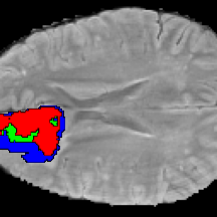

Current research on deep learning for medical image segmentation exposes their limitations in learning either global semantic information or local contextual information. To tackle these issues, a novel network named SegTransVAE is proposed in this paper. SegTransVAE is built upon encoder-decoder architecture, exploiting transformer with the variational autoencoder (VAE) branch to the network to reconstruct the input images jointly with segmentation. To the best of our knowledge, this is the first method combining the success of CNN, transformer, and VAE. Evaluation on various recently introduced datasets shows that SegTransVAE outperforms previous methods in Dice Score and $95\%$-Haudorff Distance while having comparable inference time to a simple CNN-based architecture network. The source code is available at: https://github.com/itruonghai/SegTransVAE.